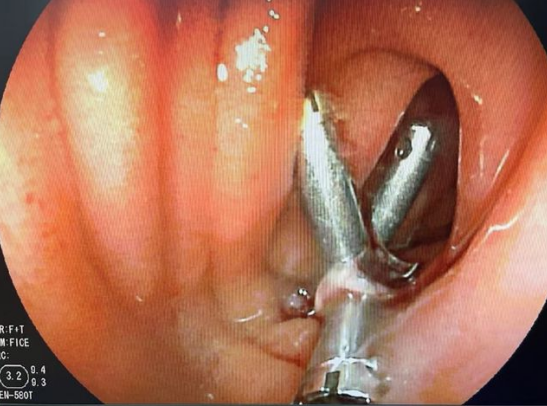

唐成祥醫(yī)生與患者家屬溝通之后,馬上為患者王大姐安排了小腸鏡手術(shù)。術(shù)中,經(jīng)肛小腸鏡的時候,發(fā)現(xiàn)回腸腺段有一個微小的破潰,魚刺已穿破小腸壁到達(dá)腹腔,形成了一個潰瘍。唐成祥醫(yī)生用鈦夾封住了創(chuàng)面。緊接著聯(lián)系了外科醫(yī)生做了個腹腔鏡,找到魚刺并取出。

唐成祥醫(yī)生表示,患者王大姐積極配合治療與檢查,所幸腸腔并沒有出現(xiàn)壞死,通過小腸鏡把創(chuàng)面封堵住,避免了外科手術(shù)的部分小腸切除。